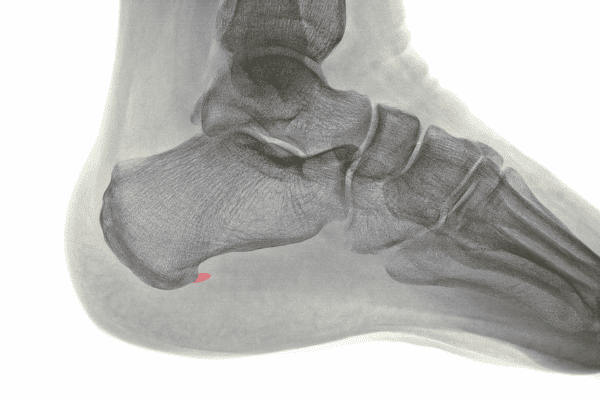

骨刺的形成大多在關節受傷和磨損後,因刺激骨膜引起發炎,破壞骨骼的生長平衡,使骨骼過度生長、鈣化,而生長出來的一小塊新骨頭就稱為「骨刺」。

骨刺好發在因長期壓力、損傷而慢慢磨損、失去彈性的地方,故常見的部位包括脊椎、肩膀、手部、臀部、膝蓋與腳部等。

絕大多數的骨刺對人體不會造成太大影響,只有大約10%機率的骨刺會因為壓迫到附近的韌帶、肌腱、神經等軟組織,引起其他症狀、造成不適(例如:痛、麻、腫脹等),而這樣的骨刺才需接受進一步治療。